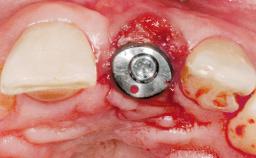

Immediate Placement of an Implant in a Maxillary Left Central Incisor Site

A 33-year-old female patient presented with an upper left central incisor that required extraction after a failed endodontic therapy. The tooth had been traumatized when the patient was a teenager and had undergone several endodontic treatments, including two apicectomy procedures. The patient was in good health and did not smoke. Clinical examination showed that the patient had a high lip line. In full smile, the gingival margins of the upper teeth were visible to the first molars. The gingival margins of central incisors 11 and 21 were only just showing. Examination of tooth 21 confirmed that the tooth was mobile and had hypererupted by 1 mm.

Type of Implants One-Piece

Placement Protocol Immediate implant placement

Tooth Site Maxillary incisor or canine

Socket Morphology Single-root socket

Socket Integrity Damage to one or more bone walls

Bone Volume Damage to one or more socket walls

Soft Tissue Contour and Volume Slightly compromised